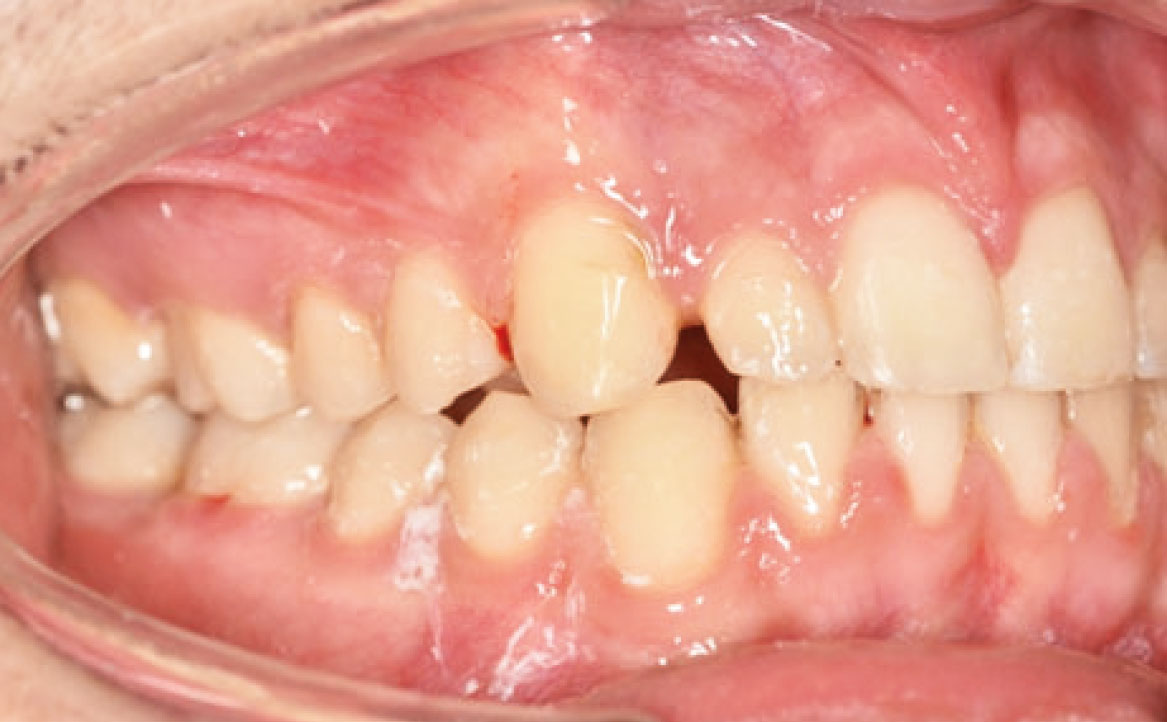

Il paziente si è presentato per la sua prima visita presso il reparto di Odontoiatria e Protesi Dentaria dell’Ospedale Vita-Salute San Raffaele diretto dal prof. E. F. Gherlone. All’esame obiettivo era evidente una malocclusione scheletrica e dentale di classe II associata a morso profondo e lieve affollamento anteriore superiore. In particolare, sono stati segnalati: rapporti occlusali di classe II, morso profondo, perdita di overjet, contrazione dell’arcata superiore e inferiore con leggero affollamento (fig. 1a-f). La richiesta del paziente era quella di migliorare l’estetica dei denti anteriori con allineatori invisibili di tipo Invisalign. Tuttavia, sia il paziente che il genitore sono stati informati che, per ragioni di efficacia e risoluzione del problema, era necessario agire anche a livello di funzionalità e risoluzione della malocclusione.

In primo luogo, sono stati prescritti entrambi gli esami radiografici ortodontici: OPT e teleradiografia latero-laterale del cranio (fig. 2a-b). Successivamente, in accordo con il genitore, è stata concordata una terapia ortodontica in due tempi. L’inizio della terapia è stato effettuato con Carriere Motion ed elastici di classe II, con l’obiettivo di migliorare la classe molare (fig. 2c-e).